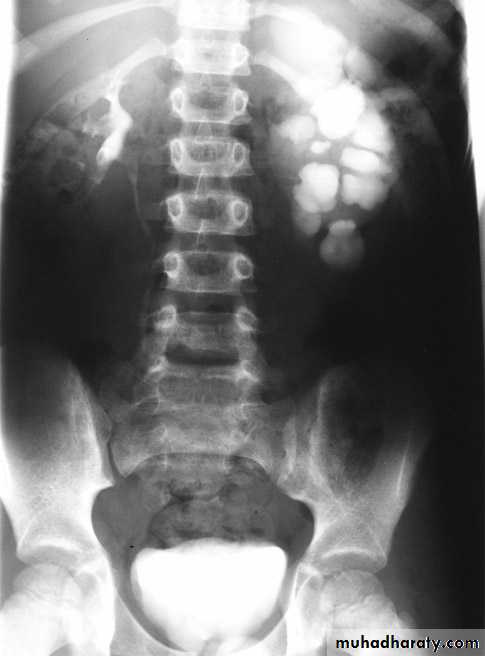

*Polycystic kidney disease